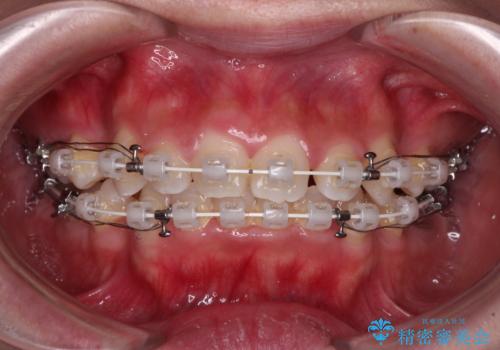

- 矯正装置

- 審美装置

- 前歯のデコボコやクロスバイト、口元の突出感を気にして来院された患者様です。

上下左右の第一小臼歯4本を抜歯して、ワイヤー装置にて矯正治療を行うこととしました。